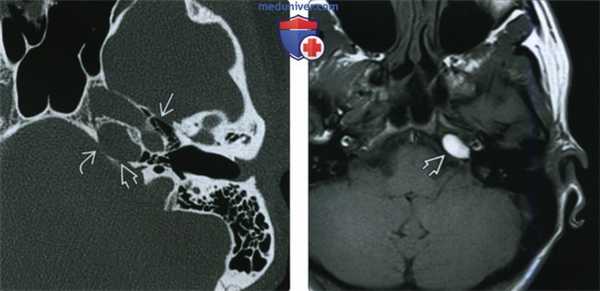

(Слева) При аксиальной КТв костном окне в пневматизированной ВП слева визуализируется холестериновая гранулема в виде хорошо отграниченного экспансивного образования овоидной формы. Задняя стенка ВА истончена или отсутствует.

(Справа) При аксиальной МРТ Т1 у этого же пациента определяется гиперинтенсивный сигнал в левостороннем экспансивном образовании овоидной формы, сопоставимом с холестериновой гранулемой.

(Слева) При КТ в коаном окне визуализируется гигантская медиальная врожденная холестеатома ВП. Обратите внимание на компоненты ВПВ, носоглотки и медиальной аенки височной кости.

(Справа) При аксиальной МРТ Т2 CISS у этого же пациента визуализируется врожденная холеаеатома с высокой и промежуточной интенсивноаью сигнала, поражающая ВПВ, медиальные отделы внутреннего уха и сосцевидный отросток. Горизонтальный каменистый сегмент ВСА смещен кпереди холестеатомой.